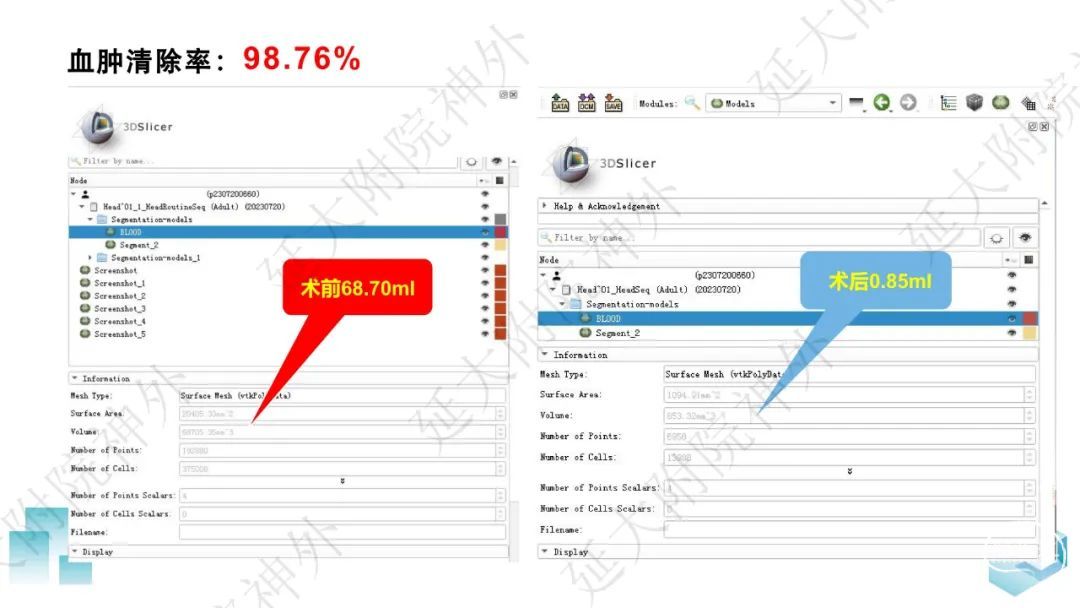

今天为大家分享的是《监测有道丨颅脑创伤-神经重症周刊》第332期,由延安大学附属医院神经外科贾云峰主任医师带来的:左侧基底节区出血破入脑室一例神经内镜下血肿清除术,欢迎阅读、分享。